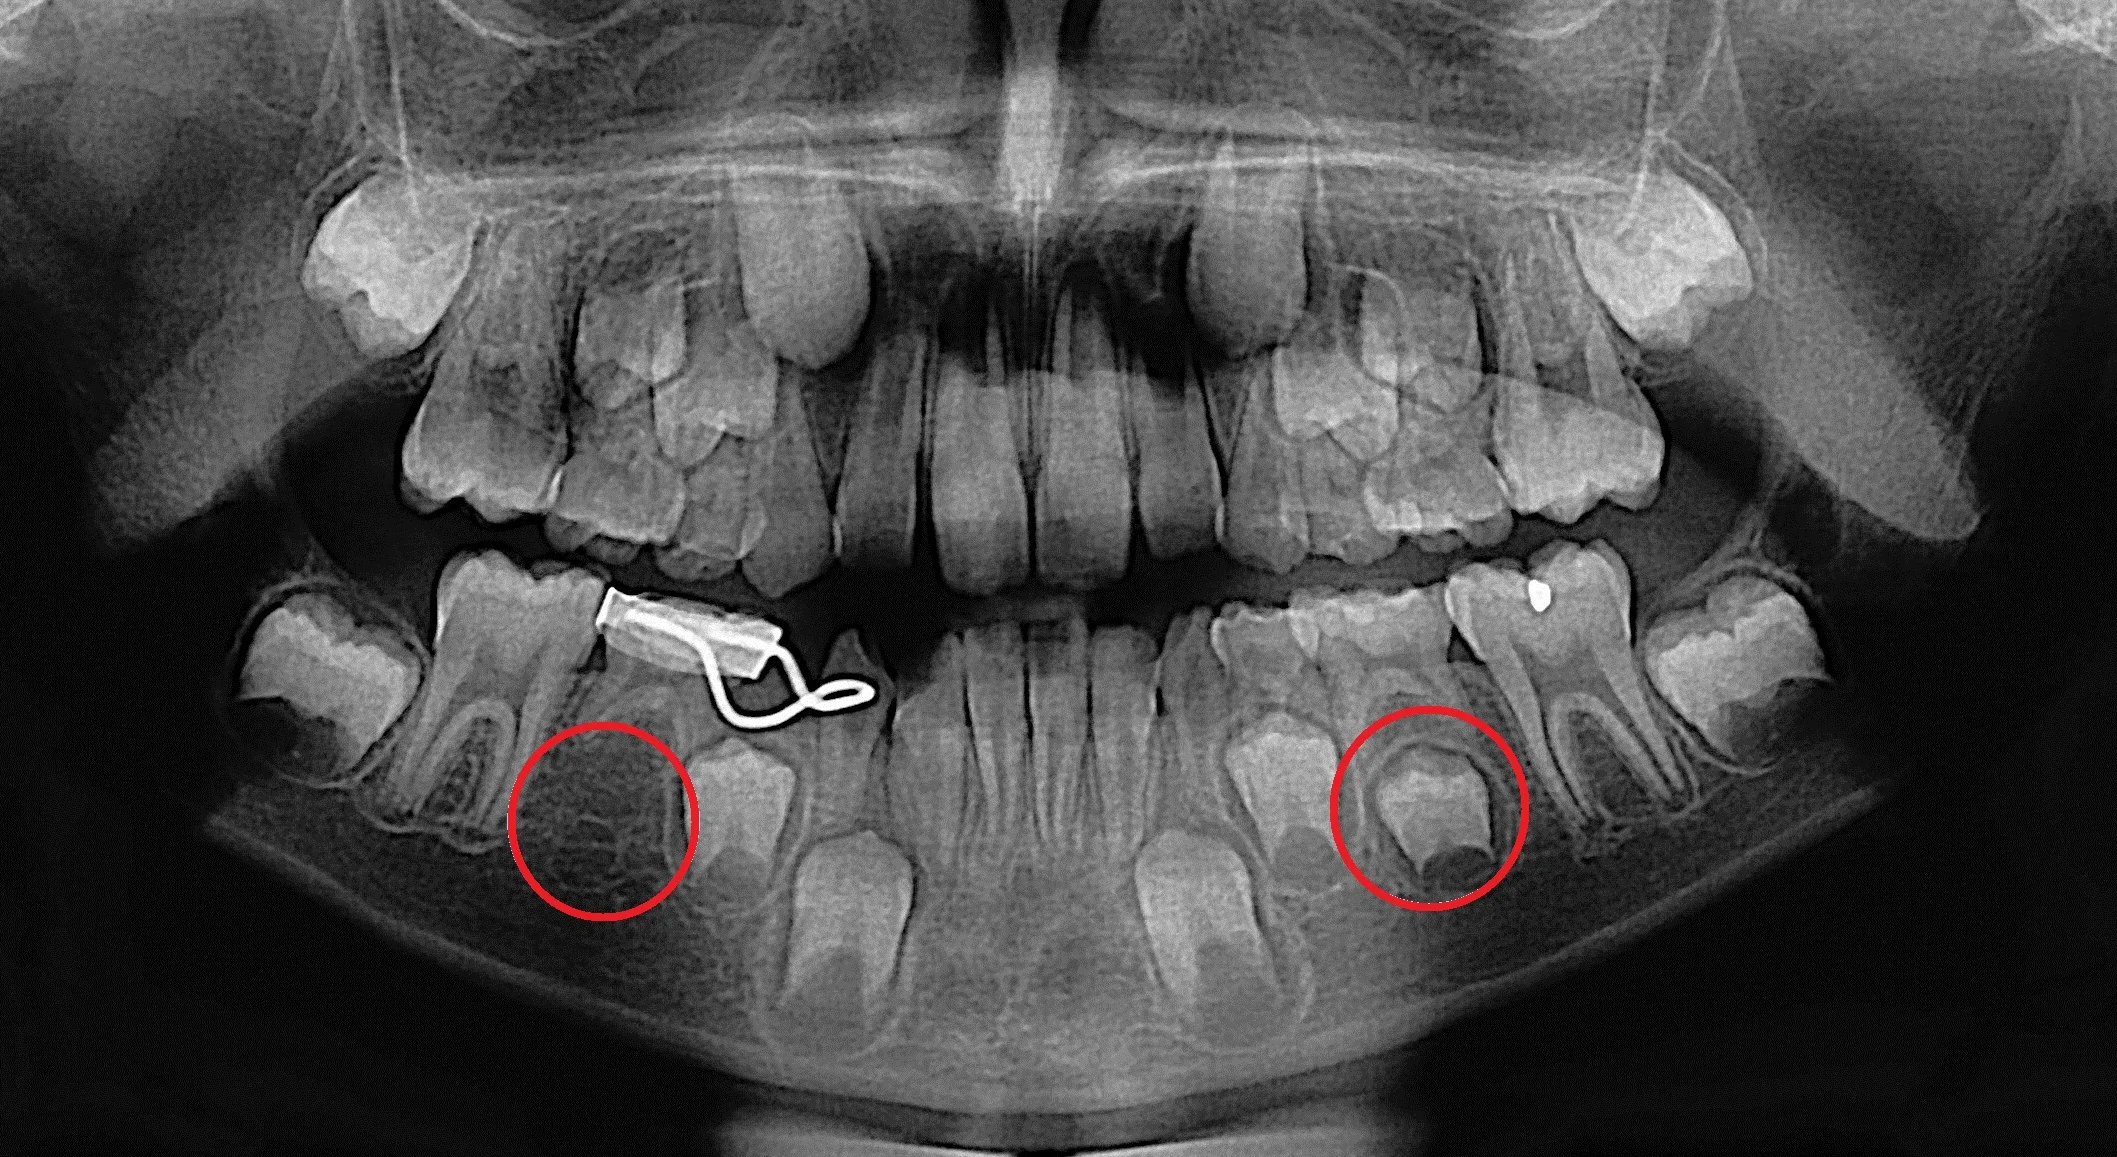

My impacted wisdom tooth Xray. r/mildlyinteresting

They are made by a panoramic X-ray machine that rotates around your head. The panoramic X-ray is commonly used to detect wisdom teeth; acquire more information about jaw issues and missing or extra teeth; help identify abscesses, cysts, and tumors; and evaluate growth and development in children. This type of X-ray also provides information.

What is Panoramic X-ray? Panoramic radiography, also called panoramic x-ray, is a two-dimensional (2-D) dental x-ray examination that captures the entire mouth in a single image, including the teeth, upper and lower jaws, surrounding structures and tissues.. The jaw is a curved structure similar to that of a horseshoe. However, the panoramic x-ray produces a flat image of the curved structure.

Panoramic: large single x-ray that shows all the teeth and the jaw bone. This kind of x-ray is used a lot in orthodontics, and in evaluating missing teeth, extra teeth and wisdom teeth. Cone Beam CT: large single x-ray that shows a 3D image of the desired area. These CT scans do produce a little more radiation than the x-rays.

A panoramic dental x-ray captures a single image that shows your teeth, jawbones and surrounding facial structures. Dentists and oral surgeons use these x-rays to diagnose dental problems and plan treatments, especially for restorative dentistry like dental implants, or teeth straightening and orthodontic work.. Here you can discover how panoramic radiography works, what to expect from the.